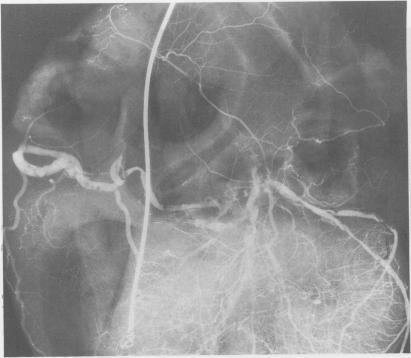

Postmortem angiography was used to examine the blood vessels supplying the sinoatrial node in 25 subjects with chronic sinoatrial disorder (group 1). The results were compared with similar studies in 54 subjects who died of heart block and in whom sinus node function was normal (group 2). Although no significant lesion obstructing the blood flow to the sinus node was seen in the majority of those in group 1, there were abnormalities in seven cases, with reduced filling of the sinus node artery in five. In group 2 the sinus node artery filled normally in all cases despite major disease of the parent vessel in three. The combination of contralateral coronary artery disease with extensive atrial anastomoses was actively sought because this arrangement might predispose to a steal phenomenon. Such conditions were fully met in three cases in group 1 and two cases in group 2, and were found to a lesser extent in a further two cases in group 1 and three in group 2. Although coronary artery disease was unlikely to be the principal cause of sinus node dysfunction in most of the cases studied it was relatively common and may have been a factor in about one third. Improved survival after myocardial infarction may increase the number of patients with chronic sinoatrial disorder of ischaemic origin.

对25例患有慢性窦房结功能障碍的受试者(第1组)进行尸检血管造影,以检查供应窦房结的血管。将结果与54例死于心脏传导阻滞且窦房结功能正常的受试者(第2组)的类似研究进行比较。尽管在第1组的大多数受试者中未发现明显阻碍窦房结血流的病变,但有7例存在异常,其中5例窦房结动脉充盈减少。在第2组中,尽管有3例患者的主干血管存在严重病变,但所有病例的窦房结动脉均正常充盈。积极寻找对侧冠状动脉疾病合并广泛心房吻合的情况,因为这种情况可能易引发窃血现象。第1组有3例、第2组有2例完全符合这些情况,第1组另有2例、第2组另有3例在较小程度上符合这些情况。尽管在所研究的大多数病例中,冠状动脉疾病不太可能是窦房结功能障碍的主要原因,但它相对常见,在约三分之一的病例中可能是一个因素。心肌梗死后生存率的提高可能会增加缺血性起源的慢性窦房结功能障碍患者的数量。